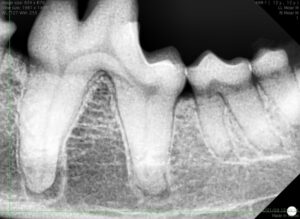

そのため、見た目だけでは分からない歯の根の周囲の様子も確認します。専用の歯科レントゲン撮影を行い歯根や周囲の骨の状態を評価しました。

あわせて歯周ポケットが深くないか歯を1本1本触れて歯肉の状態も診断します(プロービング)。

幸いなことに歯周病が重度に進行した歯はなく、今回は抜歯の必要もないことが分かりました。